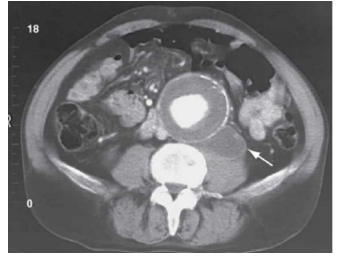

Paciente masculino, 70 anos, tabagista e hipertenso, com histórico

de revascularização miocárdica há 5 anos, deu entrada no serviço

de emergência com dor abdominal com irradiação dorsal de início

agudo há duas horas, sensação de plenitude, sem melhora com

uso de analgésico.

Realizada tomografia que reproduziu a seguinte imagem:

Com base no quadro clínico e na imagem, assinale a opção que apresenta o diagnóstico mais provável para o caso.